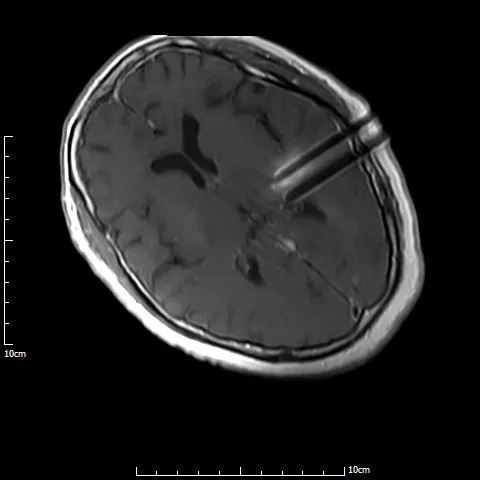

磁共振图清晰显示了满女士手术后复发病变情况

医生说,该病变在脑内位置较深,与周围组织关系复杂,手术完全切除难度较大。

术中磁共振显示,4根穿刺针平行准确穿刺至病灶内